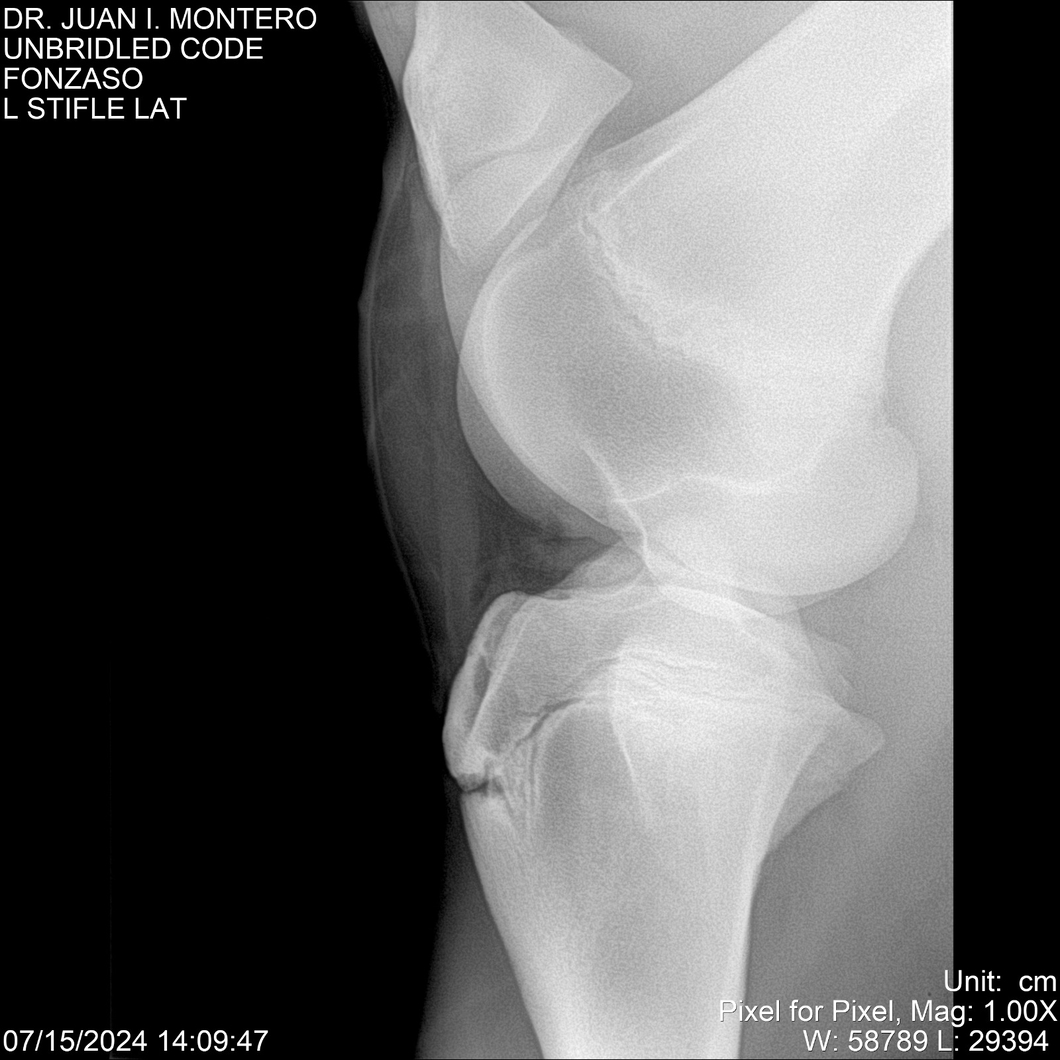

• Empresa: Abelenda N. R., Walter Hugo